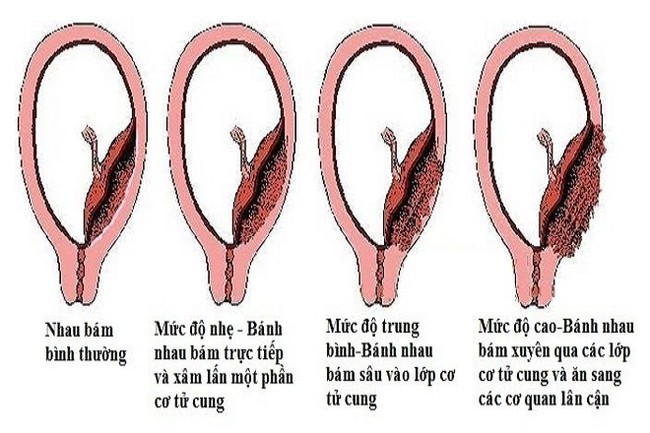

Dựa trên mức độ xâm lấn của bánh nhau, nhau cài răng lược có thể phân chia thành 3 thể chính:

- Accreta: Đây là thể nhẹ. Ở thể này, bánh nhau bám trực tiếp lên bề mặt tử cung. Theo các thống kê, thể Accreta chiếm khoảng 79% các trường hợp nhau cài răng lược

- Increta: Đây là thể trung bình. Ở thế Increra, bánh nhau xâm nhập sâu vào trong cơ tử cung nhưng chưa qua khỏi lớp thanh mạc tử cung. Thể này chiếm khoảng 14% các trường hợp bị nhau cài răng lược.

- Percreta: Đây là một thể nặng. Theo đó, bánh nhau xâm lấn xuyên qua lớp thanh mạc tử cung và xâm lấn đến những cơ quan lân cận như ruột hay bàng quang. Thể này chiếm khoảng 7% các trường hợp.

Nhau cài răng lược được phận chia thành 3 thể từ nhẹ tới nặng - Ảnh Internet.